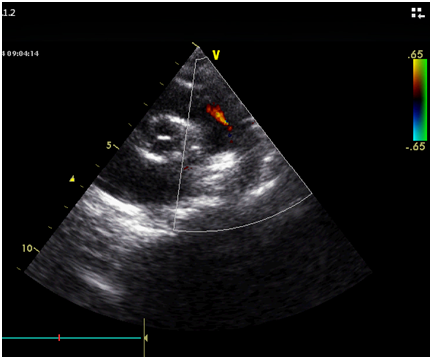

The day prior to cardiac catheterization, echocardiography showed Tiny PDA (Figure 8).

Figure 8 Echocardiograph, short axis view showed tiny PDA.